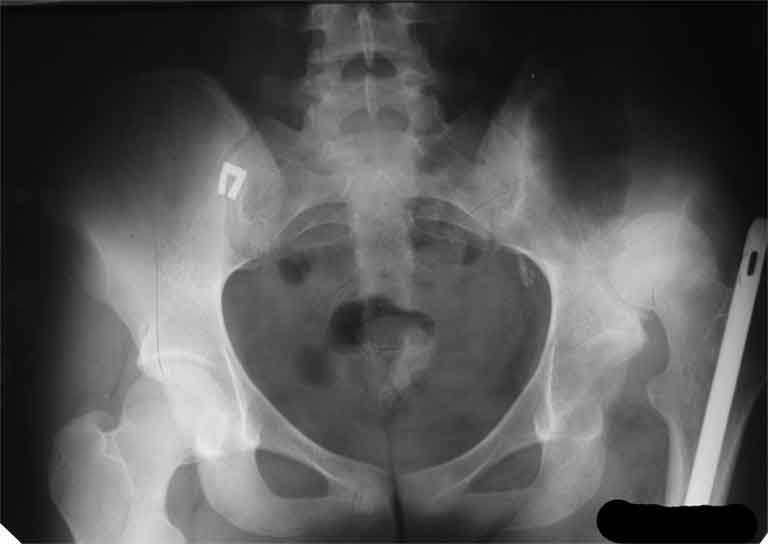

Еще пара фото, ситуация несколько иная, задачи те же, открытое вправление застарелого вывиха в 2002, молодой возраст. Сейчас госпитализирована для эндопротезирования.